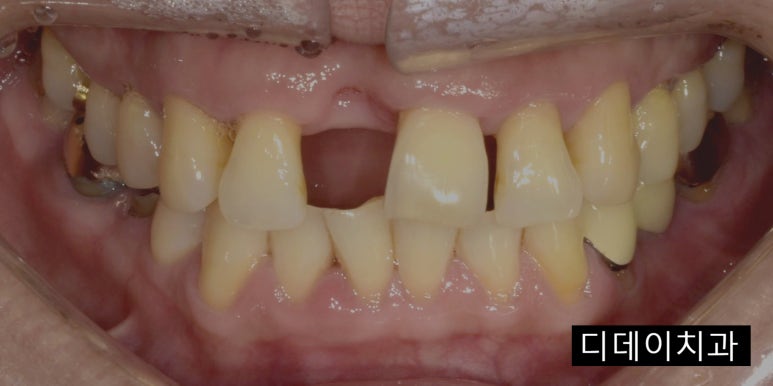

치아가 상실된 상태에서 내원해주신 케이스

2023-03-03

하지만 만약 임플란트 해야하는 치아가 엑스레이 상에서 확인이 되지 않는다면 문제가 될 수 있어요.

다른 치과에 해당 치아를 발치했다는 기록이 있고, 엑스레이로도 확인이 가능한 경우라면 괜찮지만

자연적으로 빠진 경우에는 보장개시일 이후 치아가 있었다는 것이 증명되지 않으니

임플란트치아보험 지급을 거절할 수도 있습니다.

그래서 만약에 치주 질환이 악화되어 치아가 자연적으로 빠졌다면

바로 가까운 치과로 가셔서 자연적으로 발치가 되었다는 소견서 또는 진단서를 받아두시는 것이 좋습니다.

또한 임플란트치아보험에서 보장을 받으려면 식립한 날짜가 아니라 치아를 발치한 날짜를 기준으로 한다는 점,

영구치는 보장이 가능하지만 유치나 사랑니는 보장 대상에서 제외된다는 점도 참고하시면 좋을 것 같네요 ^^

보험에 따라 다르지만 치아 머리도 남아있어야 보장이 가능하고, 뿌리만 남아있는 경우에는 보장이 되지 않기도 합니다.